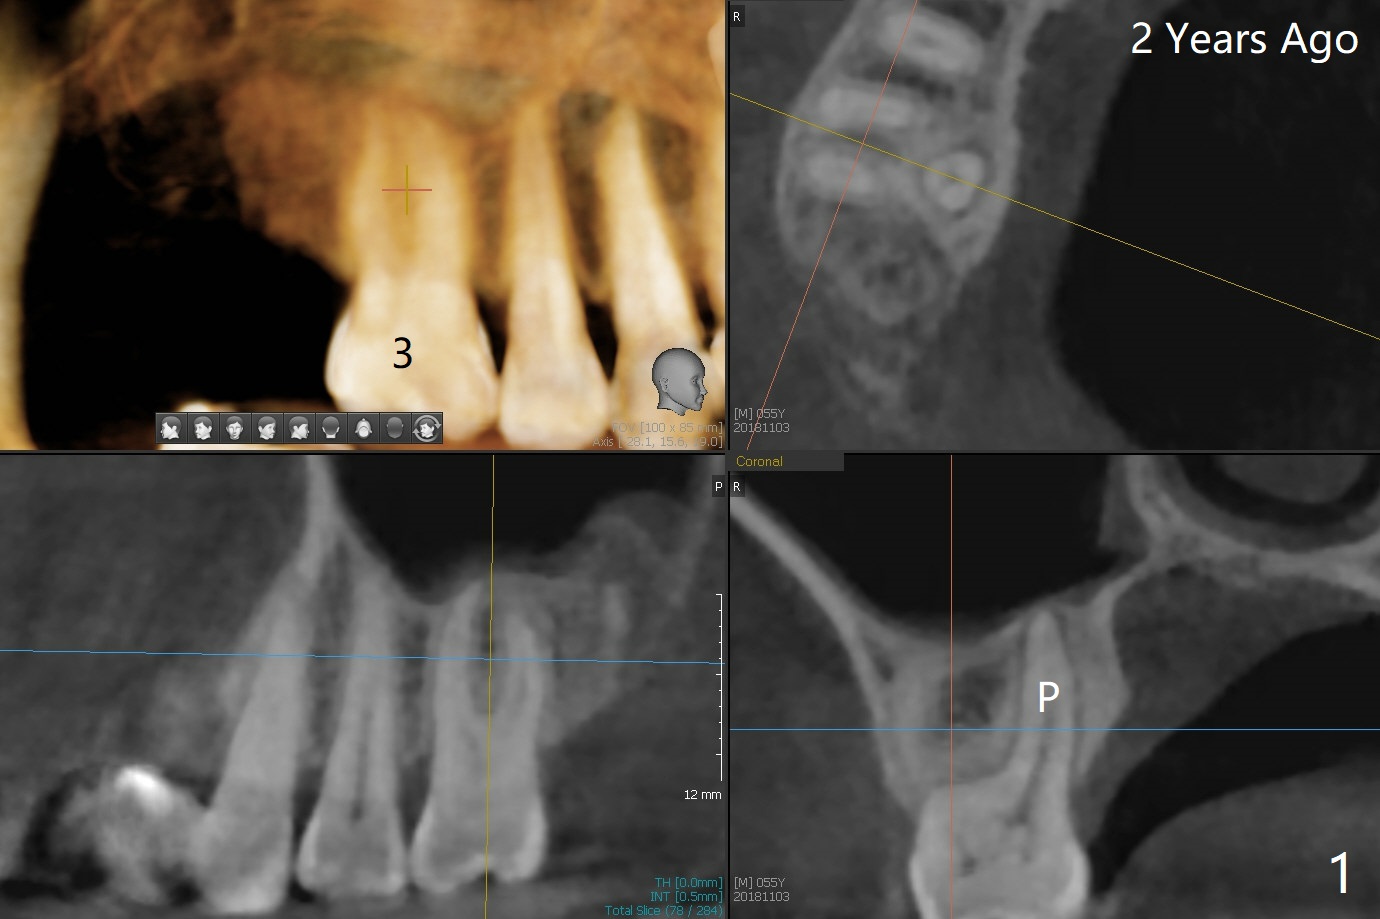

拔牙也有困难,虽然十分松动,但是无法脱位,研究两年前CT,牙根长,弯曲(图一,二),分根后才完成拔除,P:腭侧。